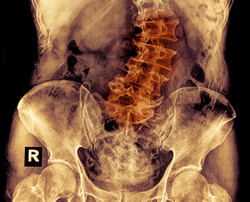

Etwa 2% bis 3% der Kinder im Alter zwischen 10 und 16 leiden unter einer Wirbelsäulenverkrümmung mit der Bezeichnung Skoliose. Skoliose kann zu emotionalen und sozialen Probleme bei Jugendlichen führen und, wenn sie nicht richtig behandelt wird, kann die Skoliose fortschreiten und zu Gesundheitsproblemen im Erwachsenenalter führen.

Das Projekt STIMULAIS(öffnet in neuem Fenster) (A novel muscular micro-electro-stimulation device for the enhanced treatment of adolescent idiopathic scoliosis avoiding bracing and invasive open surgery) konzentrierte sich auf die Entwicklung einer alternativen Behandlung für jugendliche idiopathische Skoliose (AIS). Durch die Muskelelektrostimulation der paravertebralen tiefen Rotatoren wird dieses Gerät enorme Verbesserung bei der AIS-Behandlung bedeuten. Es wird nicht nur das Fortschreiten der Krümmung stoppen, sondern sie auch korrigieren. Darüber hinaus stellt das Stimulationsprotokoll eine Innovation der Technologie mit Sensorelektromyographie (EMG) und motorischer Funktion durch eine Rückkopplungsschleifensteuerung dar. Mit dieser Funktion kann das Gerät in Echtzeit angepasst werden und die Wirksamkeit der Stimulation aufrecht erhalten werden, was eine maßgeschneiderte Behandlung für den Patienten bedeutet. Ein weiterer Durchbruch des Gerätes ist die geringe Größe und die minimal invasive Prozedur für seine Implantation. Das Projekt schuf ein Konsortium aus Mitgliedern mit abwechslungsreichen und wesentlichen Kompetenzen für eine erfolgreiche Zusammenarbeit während der gesamten Forschungs- und Entwicklungsaktivitäten. Die Wissenschaftler nahmen ihre Ziele in drei Stufen in Angriff: Schaffung wissenschaftlicher Erkenntnisse, Entwicklung von Komponenten und Prototypen sowie die Integration und Validierung des chirurgischen Eingriffs zur Implantation und die endgültige Technologie. Die Forschungen sollten eine optimale Kombination der technischen Parameter für eine erfolgreiche Elektrostimulationsbehandlung sicherstellen. Hierzu dienten Aktivitäten wie die Analyse von EMG-Daten zur bioelektrischen Muskelaktivität, um die Beziehungen zwischen EMG-Daten und Elektrostimulation zu charakterisieren. Die resultierende Analyse kann für das Stimulationsprotokoll der Wirbelsäule als Eingabe verwendet werden. Verschiedene Mitglieder des Konsortiums arbeiteten auch an den verschiedenen Teilen der Geräteentwicklung. Die Hardwarekomponenten, der Stimulationsprotokoll-Algorithmus, die Definition des aktuellen Verfahrens und verschiedene andere Aspekte wurden von verschiedenen Mitgliedern durchgeführt. Die übrigen Aufgaben umfassen den Bau des Funktionsprototypen, der externen Steuerkonsole und der für den minimal invasiven Eingriff notwendigen chirurgischen Instrumente. STIMULAIS wird den kleinen und mittleren Unternehmen des Konsortiums zusätzliche Fähigkeiten geben, Wertsteigerung sowie Wettbewerbsfähigkeit fördern und verbesserte technologischen Fähigkeiten zur Verfügung stellen. Das Projekt und das Gerät werden auch Europa insgesamt zugutekommen, da die Vermeidung von Operationen und Kosteneinsparungen viele positive wirtschaftliche und soziale Folgen haben. Die wichtigste wird die Verbesserung der Lebensbedingungen von vielen Kindern mit AIS sein.